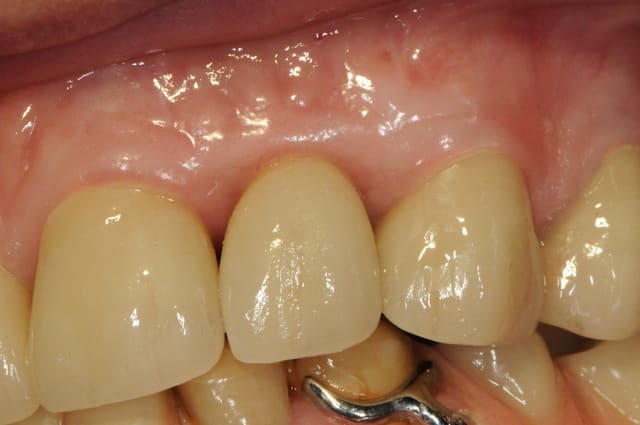

je profite de l'occasion pour vous montrer la cicatrisation gingivale autour de 22 à j+15

çà se passe plutôt très bien! si tu peux, fais-nous un petit suivi photographique de l'évolution des papilles.